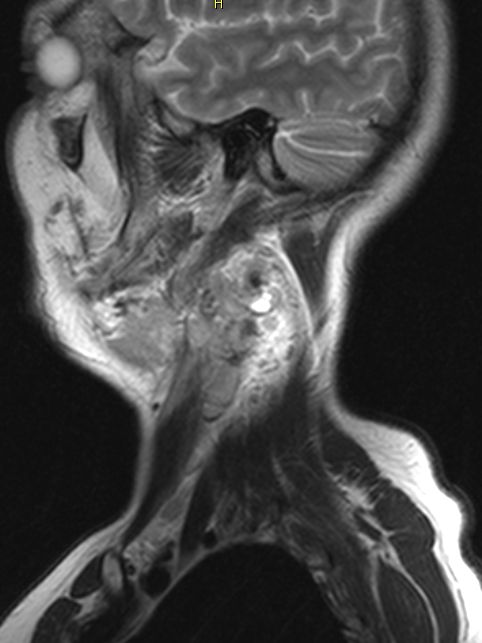

Hals-CUP 49jährige Frau mit Metastasen eines schleimbildenden Adenokarzinoms.